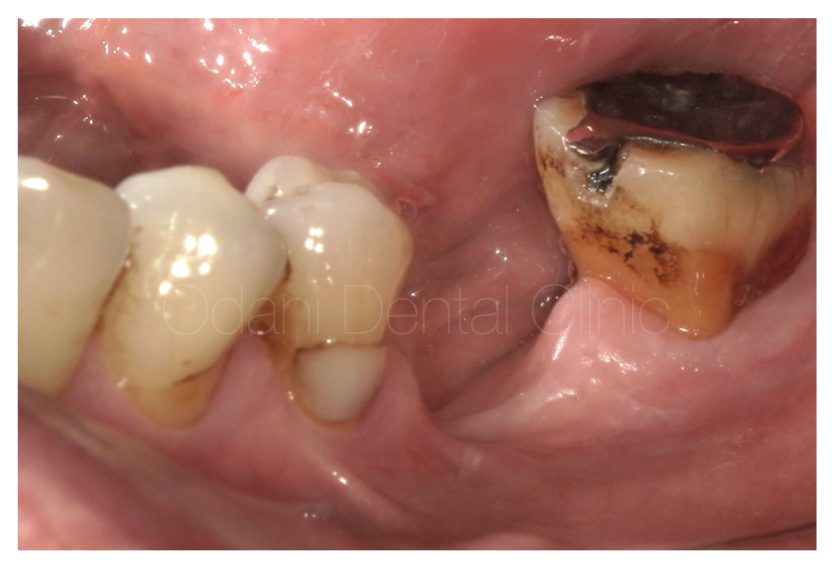

こちらは重度歯周病のために歯と周囲の骨を喪失された方で、抜歯後に甚大な歯ぐきの凹みを生じております。

このように歯ぐきが大きく不足している場合(青色の点線)、そのままの歯ぐきの状態で進んでしまうと「磨けない」=「長持ちにつながらない」結果が予測されますので、歯ぐきを歯肉移植により再生し、ゴシゴシ磨けて長期安定する環境づくりに努めます。